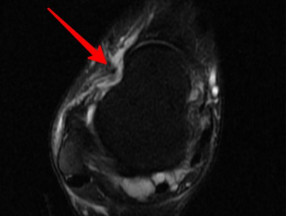

韌帶斷裂

幾經(jīng)輾轉(zhuǎn),李先生來到廣安醫(yī)院就診,骨科中心主任羅軍副主任中醫(yī)師為他進(jìn)行了詳細(xì)專業(yè)的查體,結(jié)合影像檢查,診斷為右踝關(guān)節(jié)不穩(wěn)(距腓前及跟腓韌帶斷裂)、右踝關(guān)節(jié)創(chuàng)傷性關(guān)節(jié)炎。羅軍主任帶領(lǐng)大家詳細(xì)分析病情之后,決定為他施行踝關(guān)節(jié)鏡下病變組織清理和距腓前韌帶、跟腓韌帶重建術(shù)。

醫(yī)生們在手術(shù)中發(fā)現(xiàn),李先生的右踝關(guān)節(jié)軟骨損傷明顯,踝關(guān)節(jié)前方及內(nèi)外側(cè)均有不同程度的骨質(zhì)增生,相互撞擊引起疼痛,同時(shí)距腓前及跟腓韌帶斷裂。手術(shù)醫(yī)生利用磨鉆,小心翼翼將引起撞擊的骨刺一一去除,然后,修復(fù)了損傷的關(guān)節(jié)軟骨,最后,為他完成了距腓前和跟腓韌帶的修復(fù)。